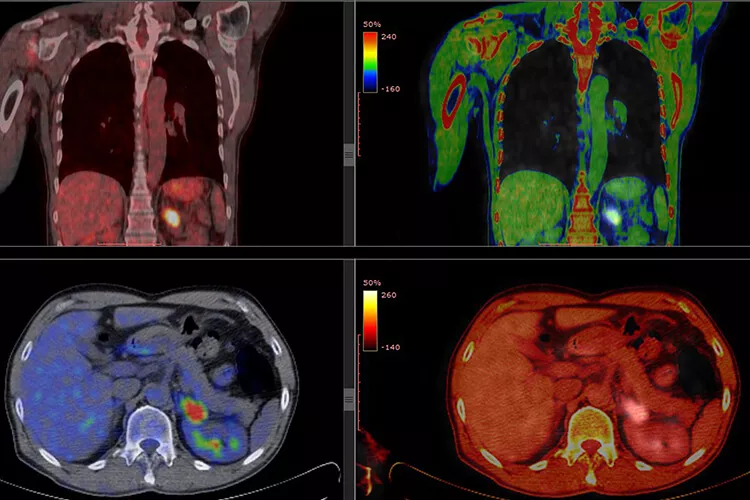

Zobrazovací metody k diagnostice mnohočetného myelomu (MM) neodmyslitelně patří již mnoho let. PET/CT je hybridní vyšetřovací metoda, která přináší informace nejen morfologické, ale i funkční. Přestože oproti magnetické rezonanci (MRI) přináší nevýhody především ve formě radiační zátěže, v posuzování rozsahu postižení skeletu má jednoznačně své místo. Co lze od PET/CT v diagnostice čekat a jak z výsledků vytěžit maximum?

Důležitost PET/CT spočívá především v tom, že přináší kombinace informací morfologických a funkčních. Skládá se v podstatě ze dvou dílčích vyšetření – pozitronové emisní tomografie (PET) a výpočetní tomografie (CT). Informace funkční zprostředkovává PET; CT slouží k rekonstrukci obrazu a korekci zeslabení ve tkáních. Provedení pouhého PET bez CT není možné, přístroje se totiž vyrábějí tak, že vždy dochází k této kombinaci metod. Obraz PET navíc bez korekce pomocí CT bývá neostrý a pro většinu lékařů špatně čitelný.

Důležité je také znát pojem SUV (standardized uptake value), který vyjadřuje jakousi kvantifikaci výsledků PET/CT, ve zkratce, „jak moc ložisko svítí“. Jak si to představit? Pomocí jednoduchého myšlenkového modelu, v němž je pacient nahrazen nádobou s vodou, do níž se aplikuje radioaktivní látka. Když se změří radioaktivita v jednom mililitru tekutiny, výsledek představuje SUV 1. Reálné výsledky, například SUV 3, ukazují násobek homogenní distribuce radiofarmaka v těle, tedy individuální míru „svítivosti“, a jsou ovlivněny složením tkání pacienta. U jedince s vyšším množstvím tukové tkáně rozhodně nedojde k homogennímu rozložení 18F-FDG a je třeba počítat s tím, že SUV vyjde jinak, než je obvyklé.

Je vhodné si uvědomit, jaká je vlastně fyziologická distribuce GLC v těle. Hodinu po intravenózní aplikaci 18F-FDG se nejvíce této látky vyskytuje v moči, konkrétně 20–40 %. Přibližně 7 % 18F-FDG bude po této době v mozku, 4,5 % v játrech a 3,3 % v srdci. Na kostní dřeň, která při vyšetření mnohočetného myelomu bude lékaře zajímat nejvíce, vychází pouze 1,7 % 18F-FDG. Ještě o něco méně GLC bude v ledvinách (1,1 %) a v plicích (0,9 %). PET/CT se provádí asi hodinu po aplikaci radiofarmaka, takže uvedená distribuce odpovídá tomu, co lze na jeho výsledcích vidět. V kostní dřeni tedy fyziologicky dochází k jistému hromadění GLC, jehož míra závisí na metabolické aktivitě kostní dřeně. Ta může být buď difúzní, nebo – jako u mnohočetného myelomu – v rámci infiltrace.

Síla PET/CT při stagingu spočívá především v hodnocení fokálních lézí nebo jasné difúzní metabolické aktivity. Velkou výhodu přináší možnost celotělového zobrazení. Problém vyvstává u non-FDG avidních mnohočetných myelomů; v tomto případě je snížena exprese hexokinázy a použití 18F-FDG tak selhává. Pomocí MRI se naproti tomu lépe hodnotí difúzní postižení a poškození v oblasti pánve a také menší ložiska kolem 5 mm. Důležité je říci, že PET/CT a MRI se skutečně v diagnostice doplňují, protože každé z těchto vyšetření vidí jiná ložiska – PET/CT „uvidí“ navíc cca 30 % lézí, ke kterým je MRI „slepá“, a stejně to platí i naopak. Ideální je proto tato vyšetření kombinovat.

PET/CT je schopna poměrně senzitivně odhalit i extramedulární postižení, což je nezávislý negativní prognostický faktor mnohočetného myelomu; nelze však zapomínat na to, že léze v extramedulární oblasti ještě nemusejí nutně znamenat právě mnohočetný myelom. Hypermetabolismus GLC totiž, kromě nádoru, provází například i zánětlivé léze; v případě difúzního postižení nebo jiných nejasností je opět vhodné PET/CT kombinovat s MRI.